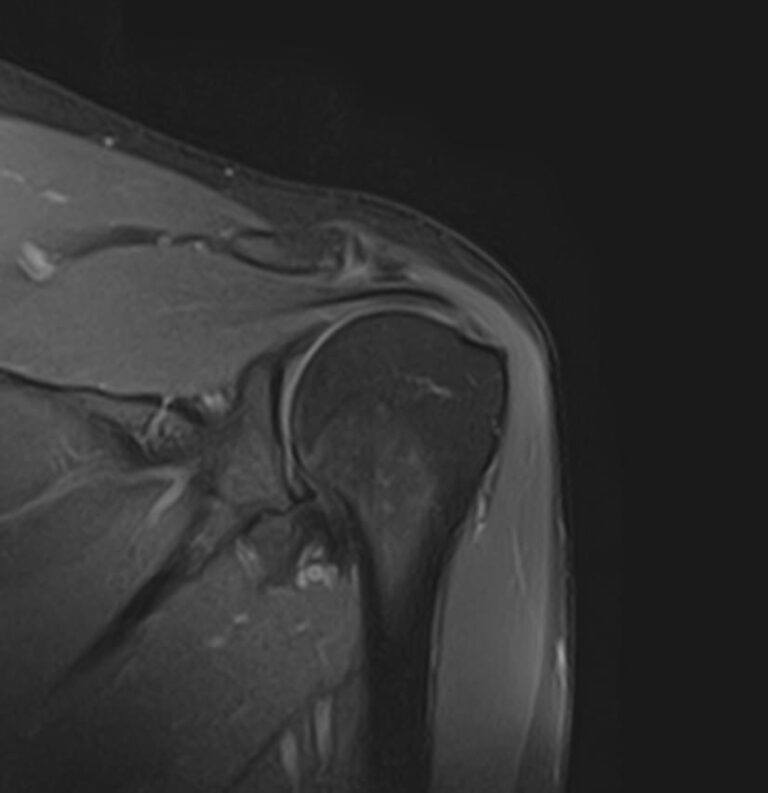

Метод МРТ позволяет оценить состояние всех анатомических областей плечевого сустава,  включая костную структуру, суставную капсулу, полость сустава с выстилающей его синовиальной оболочкой, связки, сухожилия, мышцы и окружающие мягкие ткани.

В клинике «Доступная медицина» исследование проводится на современном высокопольном томографе закрытого типа TOSHIBA VANTAGE TITAN 1,5 Тесла с превосходной  разрешающей способностью, которая обеспечивается высокой индукцией магнитного поля. Аппарат выполняет сканирование послойно в различных плоскостях и на основе этого создает 3D-изображения с высочайшей точностью и достоверностью, что позволяет эффективно ставить диагноз и назначать необходимое лечение.